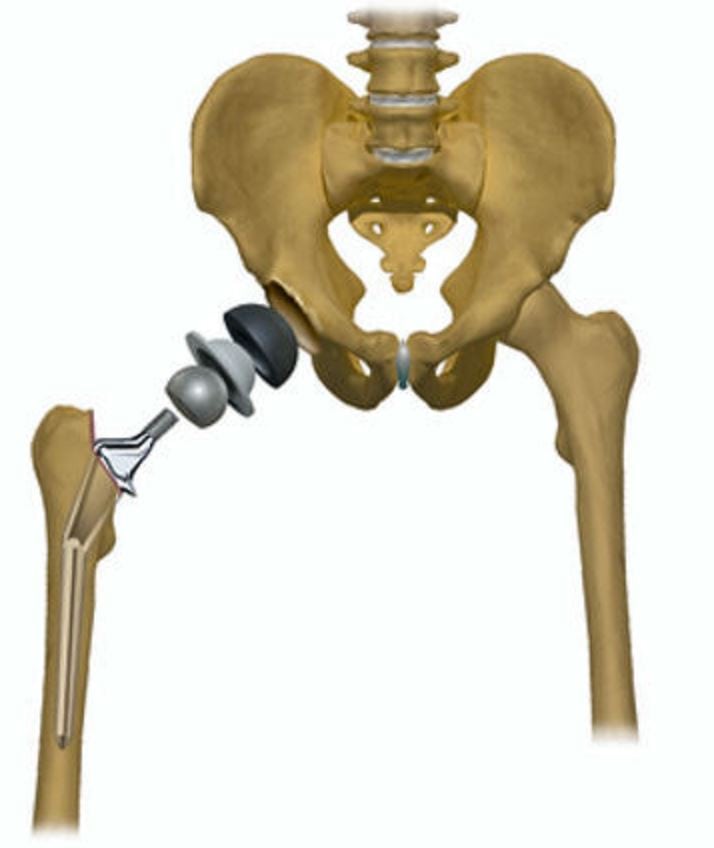

Больным с 3 степенью тяжести сразу рекомендуется прибегнуть к хирургическому вмешательству — замене разрушенного сустава эндопротезом.